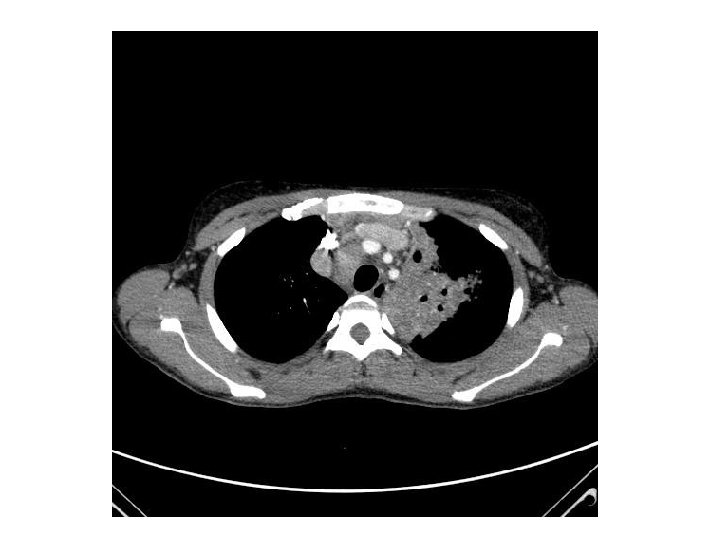

• Traitement de la tuberculose pulmonaire – Quadrithérapie débutée le 07 mai 2011 • Traitement de l’infection par le VIH – Truvada® Sustiva® le 19 mai 2011 (J 12) • Le 24 mai 2011 – Persistance de la fièvre (T=39 -41°C) – Scanner thoraco-abdomino-pelvien • Syndrome de masse ganglionnaire hilaire bilatéral sous carénaire, loge de Barety, latéro-trachéal et médiastinal • Foyer de condensation pulmonaire gauche • Transfert au CHU le 27 mai 2011

• Suspicion de surinfection bactérienne – Tazocilline®, Vancomycine®, Amiklin® débutée le 28/05 • En l’absence d’amélioration – Médiastinoscopie le 06/06: biopsie d’un ganglion de la loge de Barety • Inflammation granulomateuse à cellules épithélioïdes, nécrosante avec présence de BAAR • Bactériologie: 1300 BAAR/champ • Absence d’argument en faveur d’une hémopathie (ana-path, cytométrie de flux) • Diagnostic: IRIS – Traitement par corticothérapie à 1, 5 mg/kg/j puis 1 mg/kg/j